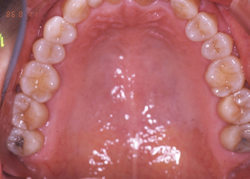

case1

8020運動「歯の長寿賞」を受賞された方の口腔内写真です。歯はもちろんのこと、歯ぐきもピンクでとてもきれいでした。そして大変お元気な、健康的な方でした。